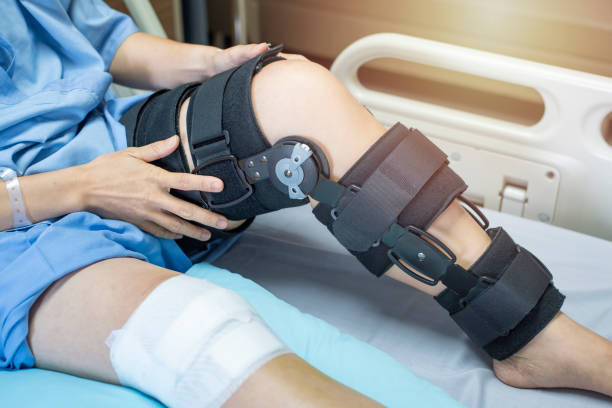

- 발목, 무릎, 골반, 고관절 운동: 이 운동은 척추를 안정화하는 데 도움이 됩니다.